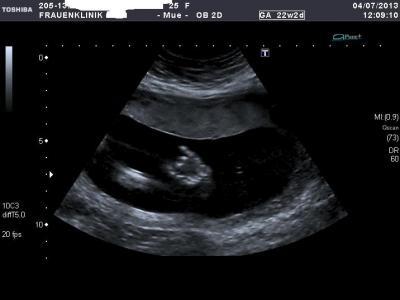

Alles bester Zufriedenheit. ich trag jetzt ca 500 gr. kleines wesen in mir :-D Wir haben alles auf CD bekommen, die Bilder und die Viseo´s :-) Wir sind super glücklich ich könnt sie mir die ganze Zeit anschauen. Hier mal ein Foto von unserem Rockerbaby. Zeige- und kleiner Finger sind Gestreckt. Der Arzt fand es total super. Da er auch gern zum Rockkonzert geht :-)

Bild zu Zurück von Feindiagnostik - Forum für November - Mamis